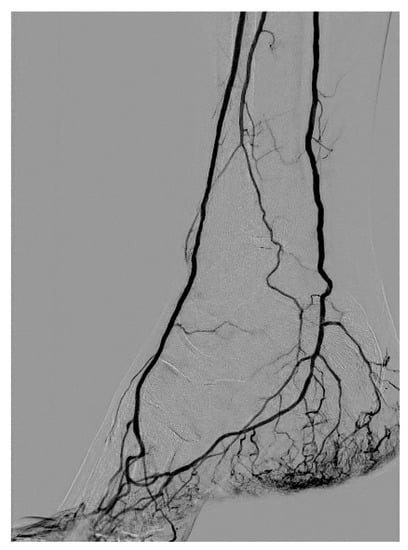

3.1. Stenosis and Occlusion

3.2. Dissection